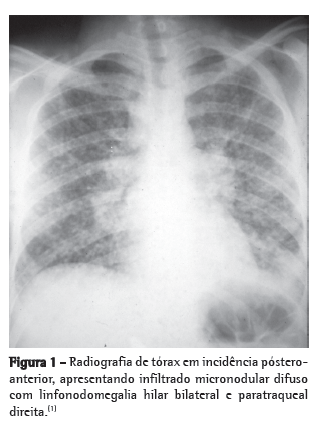

Os exames radiográficos não são específicos para o diagnóstico dessa micose. Na histoplasmose pulmonar aguda, o aspecto radiográfico mais frequente é a presença de linfonodomegalias hilares bilaterais e mediastinais associadas a infiltrado reticulonodular peri-hilar bilateral (Figura 1). Porém, linfonodomegalia hilar unilateral, infiltrado intersticial reticulonodular difuso, cavidades e nódulos difusos ou isolados podem ser encontrados. Na histoplasmose pulmonar crônica, o aspecto radiográfico se assemelha ao da tuberculose do adulto ou de reinfecção, isto é, infiltrado progressivo em lobo superior, cavidades e sinais de fibrose. O alargamento do mediastino pode ser visto principalmente na TC de tórax nos casos de histoplasmose granulomatosa e fibrose mediastinal. Nódulo solitário ou nódulos múltiplos com calcificação central são muito característicos da forma nodular, isto é, do histoplasmoma.(1-5)

A histoplasmose, nas suas formas agudas, é uma doença de regressão espontânea. A forma assintomática ou pouco sintomática é a mais frequente da doença, e muitas vezes passa despercebida por ser confundida com a gripe. A forma dita de histoplasmose pulmonar aguda ou epidêmica pode se apresentar ao clínico como casos isolados, de difícil diagnóstico, ou sob a forma de microepidemias, de mais fácil diagnóstico, de curso benigno, cujos sintomas são dependentes de uma maior ou menor exposição aos propágulos infectantes. Febre, tosse pouco produtiva persistente, cefaleia, astenia, dor retroesternal e prostração intensa são frequentes. A palidez cutânea é um sinal marcante. O aumento dos gânglios linfáticos superficiais e a hepatoesplenomegalia são achados característicos da forma pulmonar difusa aguda. Os sinais físicos pulmonares são inexpressivos. O período de incubação varia de 3 a 14 dias. Os achados radiológicos mais frequentes nessa forma são as linfonodomegalias hilares bilaterais com infiltrado reticulonodular bilateral. Quando a linfonodomegalia hilar é unilateral, esse aspecto é indistinguível do complexo primário da tuberculose pulmonar.(2,5-8).